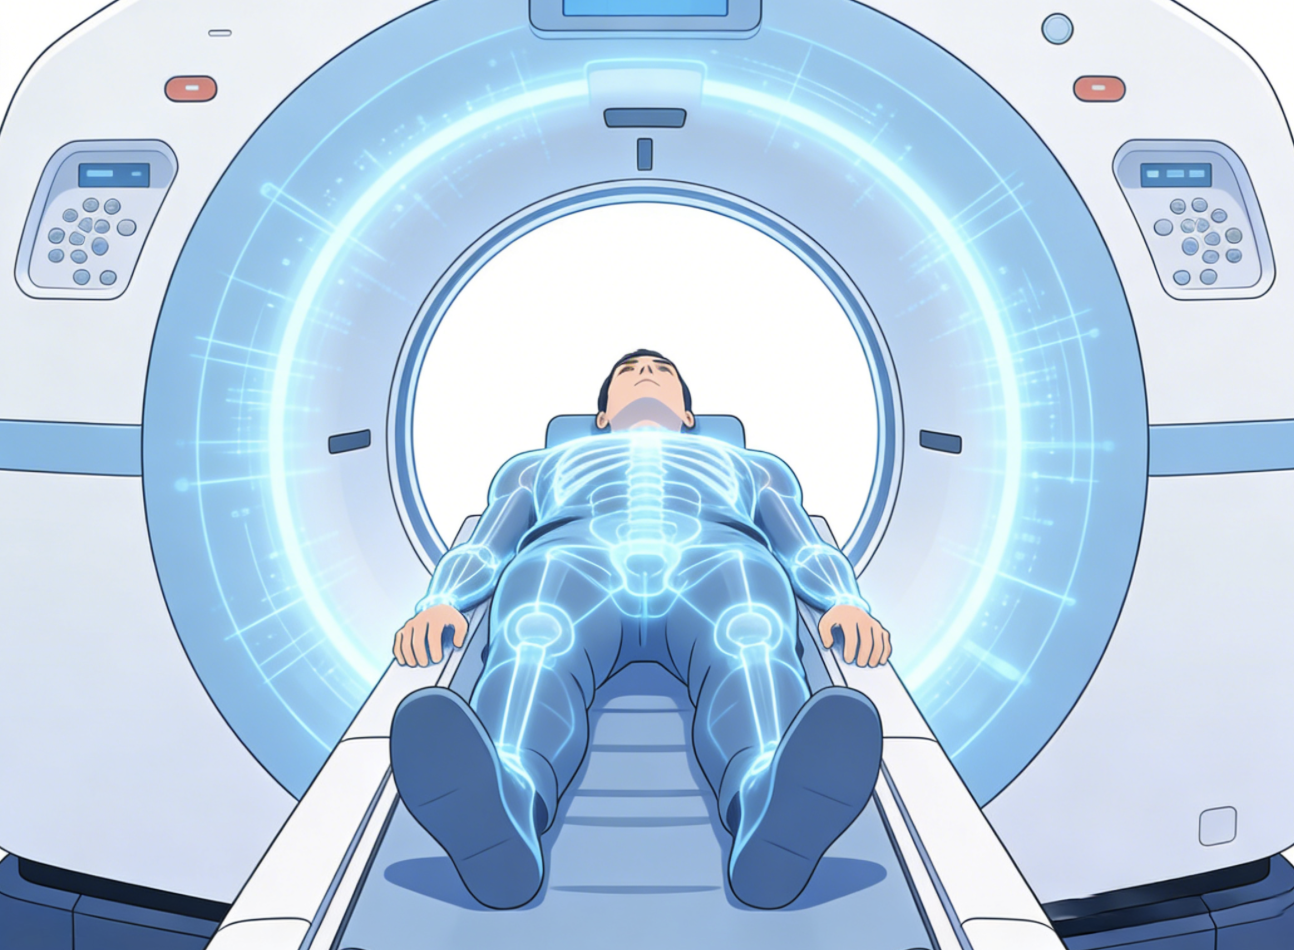

肺癌病理报告主要用于判断肿瘤类型、活跃程度及扩散风险。通过病理类型、分化程度、淋巴结转移、胸膜侵犯、脉管癌栓及 PD-L1 表达这...[详情]

TAG标签:病理报告 治疗方向